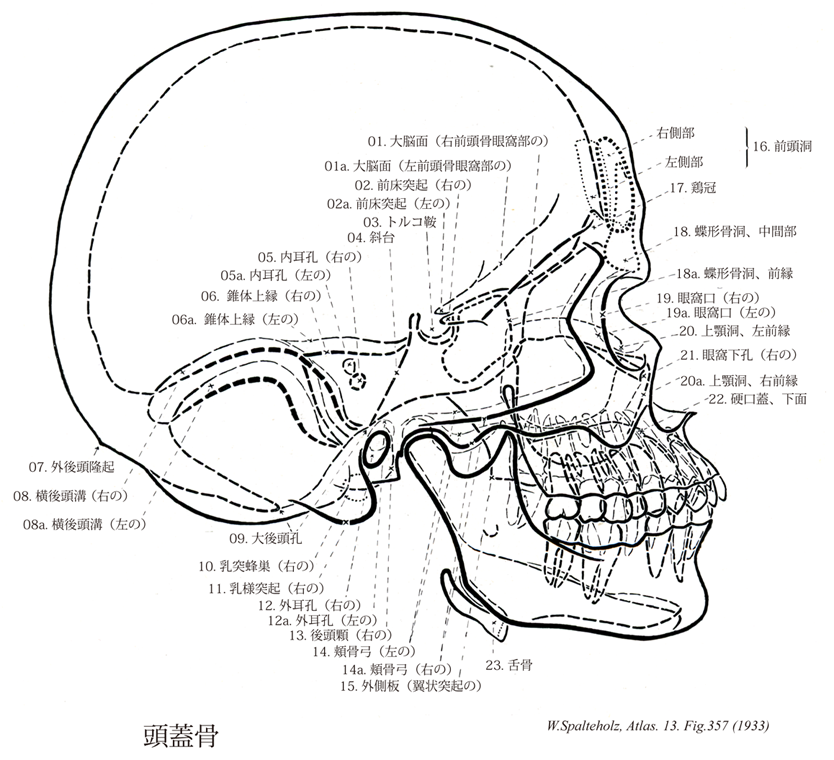

Spalteholz HANDATLAS DER ANATOMIE DES MENSCHEN VON WERNER SPALTEHOLZ

357

- 357_00【Bones of cranium; Skull bones頭蓋骨;ズガイコツ Ossa cranii】

→(頭蓋は15種23個の骨、すなわち10種16個の頭蓋骨および5種7個の顔面骨とにより形成されている。頭蓋骨は中枢神経系および感覚器に接する部分を形成する骨格で後頭骨(1個)、蝶形骨(1個)、側頭骨(1対2個)、頭頂骨(1対2個)、前頭骨(1個)、篩骨(1個)、下鼻甲介(1対2個)、涙骨(1対2個)、鼻骨(1対2個)、及び鋤骨(1個)である。頭蓋を構成する骨の分類には諸学者による見解の相違があり、後頭骨、蝶形骨、側頭骨、頭頂骨、前頭骨の5種7個を脳頭蓋とし、他の10種16個を顔面骨とする意見もある。)

- 357_01【Internal surface of frontal bone内面;大脳面(前頭骨の) Facies interna; Facies cerebralis】 Surface of the frontal bone that faces the brain.

→(前頭骨の内面は後方を向くくぼんだ面で、脳の前端を容れるところとなる。軽度の脳隆起、指圧痕、樹枝状の中硬膜動脈溝などを見る。)

- 357_02【Anterior clinoid process前床突起;小翼突起 Processus clinoideus anterior; Processus alae parvae】 Projection from the lesser wing of the sphenoid bone that is directed posteriorly toward the middle and posterior clinoid processes.

→(蝶形骨小翼の後縁は遊離縁をなし、その内側端に視神経管の後外側から後内側に向かう前床突起がある。)

- 357_03【Sella turcicaトルコ鞍 Sella turcica】 It is located above the sphenoidal sinus and houses the pituitary gland.

→(トルコ鞍は蝶形骨体上面には、トルコ風の馬の鞍に似ている骨隆起で中頭蓋窩の中央部にある。この骨のくぼみには、重要な内分泌腺の一つである下垂体が入る。)

- 357_04Blumenbach, Clivus of【Clivus斜台 Clivus】 Bony structure that slopes downward from the dorsum sellae to the foramen magnum. It is formed by the occipital bone and the sphenoid.

→(後頭蓋窩の正中部では中頭蓋窩の後端である鞍背から後方に大後頭孔まで「すべり台」のような急な斜面がある。これが斜台で、その上半は蝶形骨、下半は後頭骨からなる(その境界は骨が癒合しているのでわからない)。)

- 357_05【Internal acoustic opening内耳孔 Porus acusticus internus】 Opening of the internal acoustic meatus in the posterior surface of the petrous part of the temporal bone.

→(錐体後面のほぼ中央にある内耳道の入口。)

- 357_06【Superior border of petrous part錐体上縁;錐体稜(側頭骨の) Margo superior partis petrosae; Angulus superior pyramidalis (Ossis temporale)】

→(錐体上縁は前上面と後上面の境となり、頭蓋腔内に突出して中頭蓋窩と後頭蓋窩の境界を作る鋭い縁である。ここに上錐体洞溝がある。上錐体静脈洞がここにはまる。)

- 357_07【External occipital protuberance外後頭隆起;後頭結節;外後頭結節 Protuberantia occipitalis externa】 Easily palpable bony projection at the border between the occipital and nuchal planes.

→(外後頭隆起は凸面をなす後頭鱗の外面のほぼ中央に外後頭隆起がある。)

- 357_08【Transverse occipital sulcus横後頭溝;横洞溝;横溝 Sulcus occipitalis transversus; Sulcus sinus transversi; Sulcus transversus】 Continuation of the intraparietal sulcus on the occipital lobe.

→(横後頭溝は後頭葉での頭頂内溝ののつづき。)

- 357_09【Foramen magnum大後頭孔;大孔 Foramen magnum; Foramen occipitale magnum】 Large opening in the occipital bone for the medulla oblongata. vessels, and nerves.

→(大後頭孔(大孔)は大きさや形に変化があるが、一般に前後に長い卵円形である。大後頭孔は頭蓋腔と脊柱管とを結ぶ孔で、したがって脳の脊髄につづく部である延髄下部が副神経脊髄根、椎骨動脈、静脈叢などとともにこれを通る。)

- 357_10【Mastoid cells; *Mastoid air cells乳突蜂巣 Cellulae mastoideae】 Pneumatized cells that, like the tympanic cavity, are lined with squamous or cuboidal epithelium.

→(側頭骨乳様突起内にある多数の小さな相通じている腔。乳様突起洞あるいは鼓室洞に連なる。鼓室と同様、扁平または立方上皮で被われる。)

- 357_11【Mastoid process乳様突起;乳突隆起 Processus mastoideus】 Projection behind the external acoustic meatus that contains the mastoid cells.

→(乳突部の大部分は、下前方に向かって突出する大きい乳様突起で占められる。その表面は胸鎖乳突筋の着くところで粗である。乳様突起の内部は成人では大部分、多数の小さい乳突蜂巣で占められる。これは生後に乳様突起の発育に伴って拡がるもので、その拡がりは個体によりかなりまちまちであり、錐体の方にもおよぶ。乳突蜂巣は互いに迷路状につながっていて、そのつづきは乳様突起の上半分にある乳突洞につながっている。乳突洞はその前方の小さい乳頭洞入口を経て、後方から鼓室の上部に開く。生体では鼓室の内面を被う粘膜の続きが乳突洞を経てすべての乳頭蜂巣の内面にまでおよんでいる。)

- 357_12【External acoustic opening外耳孔;骨外耳孔 Porus acusticus externus】 Opening to the external acoustic meatus.

→(外耳道を作るときに前後両縁が中央部より速く発育し、その尖端で癒合するために、ある時期には外耳道下壁の骨板に孔を有することがある。)

- 357_13【Occipital condyle; *Condyle後頭顆 Condylus occipitalis】 Spherical eminence for articulation with the atlas.

→(後頭骨下面にある2つの細長い卵形をした関節面を有する高まりが後頭顆である。これは第1頚椎の上関節窩と関節する。)

- 357_14【Zygomatic arch頬骨弓 Arcus zygomaticus】 Arch formed by the zygomatic process of the temporal bone and the temporal process of the zygomatic bone.

→(眼窩の外側方には、眼鏡のつるのような骨の橋がある。これが頬骨弓で、その後端は耳の孔(外耳孔)の近くまで達している。頭蓋を正面から見ると、顔面は頬骨弓の所が最も広く、それよりも下方では急に幅が狭くなっている。頬骨の側頭突起が頬骨の後下部より後方に突出し、側頭骨の頬骨突起と連結して形成された骨弓をいい、ほぼ水平位にある。側頭突起と頬骨突起間にある前方により後方へ斜走する縫合を側頭頬骨縫合という。頬骨弓からは咀嚼筋の一つである咬筋が起こり下顎角の咬筋粗面につく。なお頬骨弓の外側方への最も突出した点を頬骨弓点といい、両側のこの点の間の距離をもって頭蓋の顔面幅最大長としている。頬骨弓の下方のくぼみにある脂肪塊(頬脂肪体sucking pad)は、普通の皮下脂肪とは違って、線維の少ないみずみずしい脂肪組織からなり、いくらを詰めたようになっている。)

- 357_15【Lateral plate of sphenoid process; Lateral pterygoid plate外側板(翼状突起の);外側翼状板 Lamina lateralis (Processi pterygoideus ossis sphenoidalis)】

→(蝶形骨の翼状突起の外側板は内側板にくらべて広く、やや短く、矢状面に対して斜めに位置する(その外面からは外側翼突筋が起こる)。外側翼突筋の下頭が起始する。内外両側板は前縁で連結し、その前面を縦に走る浅い翼口蓋溝は翼状突起が上顎体および口蓋骨垂直板と合してつくる翼口蓋窩の後壁をつくる。また、内外両側板は後方に開いた翼突窩をつくる(ここから内側翼突筋が起こる)。しかし、内側板と外側板とはその下部では離れて翼突切痕をはさむ。ここには口蓋骨の錐体突起がはまりこんでこれを補う。外側板の後縁は鋭く、その上部から小さい翼棘突起を出すことが多い。)

- 357_16【Frontal sinus前頭洞 Sinus frontalis】 It is an average of 3 cm high, 2.5 cm wide, and often extends 1.8 cm posteriorly, forming part of the roof of the orbit.

→(前頭洞は眉間の辺りにある副鼻腔をなす空洞。篩骨漏斗により同側の中鼻道に連なる。)

- 357_17【Crista galli鶏冠 Crista galli】 Small bony projection in the cranial cavity to which the falx cerebri is firmly attached.

→(篩板上面の正中線で、横からみると三角形の鋭い鶏冠が頭蓋腔に向かって突出する。)

- 357_18【Sphenoidal sinus蝶形骨洞 Sinus sphenoidalis】 Paired sinus in the body of sphenoid that varies in size. It opens at the spheno-ethmoidal recess.

→(蝶形骨体の内部は殆ど蝶形骨洞でしめられ、空洞である。その大きさは不定で、ときには体の後に結合する後頭骨の底部にも進入している。蝶形骨洞は蝶形骨体部の頭蓋底部に位置する副鼻腔である。思春期以降に発達し、成人にて含気化が顕著になるが、含気の程度にバリエーションがあり、視神経管周囲・視神経が隣接しており、(内頚動脈が走行している)頚動脈隆起・視神経管の骨性隆起、その間に視神経管頚動脈裂optico-carotid recessとよばれる陥凹が蝶形骨内面より観察される。)

- 357_19【Orbital opening眼窩口;眼窩入口 Aditus orbitalis】 Anterior opening of the orbital cavity.

→(眼窩が顔面に開く眼窩口は外側縁が少し下がった四角形である。 左右の眼窩口はほぼ四角形で、眼窩上縁、眼窩下縁、内側縁および外側縁をもつ。)

- 357_20Highmore, Antrum of【Maxillary sinus上顎洞;ハイモア腔 Sinus maxillaris】 It measures over 3 cm vertically and sagittally and 2.5 cm in the frontal plane. Its floor is usually at least 1 cm below the floor of the nose and its lowest point is usually at the level of the first molar.

→(上顎洞は上顎体中にある最大の副鼻腔で、その形はだいたいにおいて上顎体の形に一致するが、尖端を外上方、すなわち頬骨突起の方に出しているので錐体状に近く、その底は鼻腔面にむく。ここにはなはだ大きい上顎洞裂孔があるが、完全な頭蓋ではこの裂孔は口蓋骨の垂直板、篩骨の鈎状突起および下鼻甲介の上顎、篩骨稜突起によりその一部がふさがれて著しく小さくなる。(生体では、さらに鈎状突起まで鼻粘膜に被われるため、中鼻甲介の下の半月裂孔に開く小さな開口を残すのみとなる。)上顎洞はその前壁が最も厚く、つぎは後壁、上壁の順で内側壁が最も薄い。下壁は歯槽突起に入り、場所によってその厚さが異なるが、大臼歯および小臼歯の歯根をおおう部、とくに第1、第2臼歯の付近で最も薄く、それらの歯根はしばしば洞に達する。また、下壁には歯槽中隔の為に多くの骨の高まりやくぼみを見るのを常とする。なお、上顎洞の前後稜壁には多くの細い歯槽溝または歯槽管および歯槽孔が見られる。『ハイモア洞』:イギリスの自然科学者Nathaniel Highmore (1613-1685)の名を冠するが、レオナルド・ダ・ビンチがすでに観察している。ハイモアは、この他にも精巣縦隔(Highmore's body)に名を残している。)

- 357_21【Infra-orbital foramen眼窩下孔 Foramen infraorbitale】 Opening of the infra-orbital canal from which the infra-orbital nerve and accompanying vessel emerge. Pressure point for the second division of the trigeminal nerve.

→(上顎体下縁は明瞭な境なしに歯槽突起に移る。眼窩下縁の下約0.5-1.0cmに眼窩下孔がある。これは眼窩面の眼窩下溝につづく眼窩下管の顔面に開く口である。)

- 357_22【Hard palate硬口蓋 Palatum durum】 Hard, bony part of the palate.

→(硬口蓋は鼻の粘膜により上部を、口腔の天井にあたる部分の粘膜により下部をおおわれた骨口蓋からなり、粘膜は厚く、骨口蓋の骨膜に硬く付着する。粘膜表面には、正中線に一致して口蓋縫線という高まりがみられ、その前端に切歯乳頭という小隆起がある。その前端に切歯乳頭という小隆起がある。口蓋血管、神経、粘膜腺を有する口蓋の前方部分。硬口蓋の前部には、3~4本の横走するヒダ、すなわち横口蓋ヒダがみられる。横口蓋ヒダはとくに幼児で明瞭に見られる。)

- 357_23【Hyoid bone舌骨 Os hyoideum】 Bone that already begins to ossify before birth.

→(下顎骨と喉頭との間で舌根部にある独立したU字形の小骨である。体、大角、小角を有する。体は舟の形を呈し、膨隆部が前方を、陥凹部が後方を向いている。前面には十字形の隆線があり、これにより4区画に分けられている。上区には外側に舌骨舌筋、内側にオトガイ舌筋がつき、下区には外側に肩甲舌骨筋、内側に胸骨舌骨筋がつく。大角は体の外側端から後上方に延びる骨片で、その先端はは肥厚する。小角は体と大角の結合部から円錐形を呈して後上方に着きだし、その先端は茎突舌骨靱帯によって側頭骨茎状突起と連結する。この靱帯はまれに骨化することがある。舌骨は系統発生的に鰓の骨格の一部に相当するもので、舌骨体の上部、小角、茎突舌骨靱帯および側頭骨茎状突起が第2臓弓軟骨、舌骨体の下部と大角が第3臓弓軟骨に由来する。Hyoideumはギリシャ語のυ(hy)に似た(eidos)という意味の形容詞。なお日本語の「舌骨」はドイツ名Zungenbeinの直訳であるが、この骨は舌の根もと(舌根)に存在して、筋肉を介して舌と密接な関係がある。)